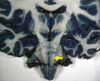

Label the types of extra-axial bleed occuring at the red; yellow & green arrows [3]

**red arrow: EDH** brown arrow shows how EDH respects the suture margins **yellow arrow points at SAH** **green arrow: SDH** blue arrow shows the fracture